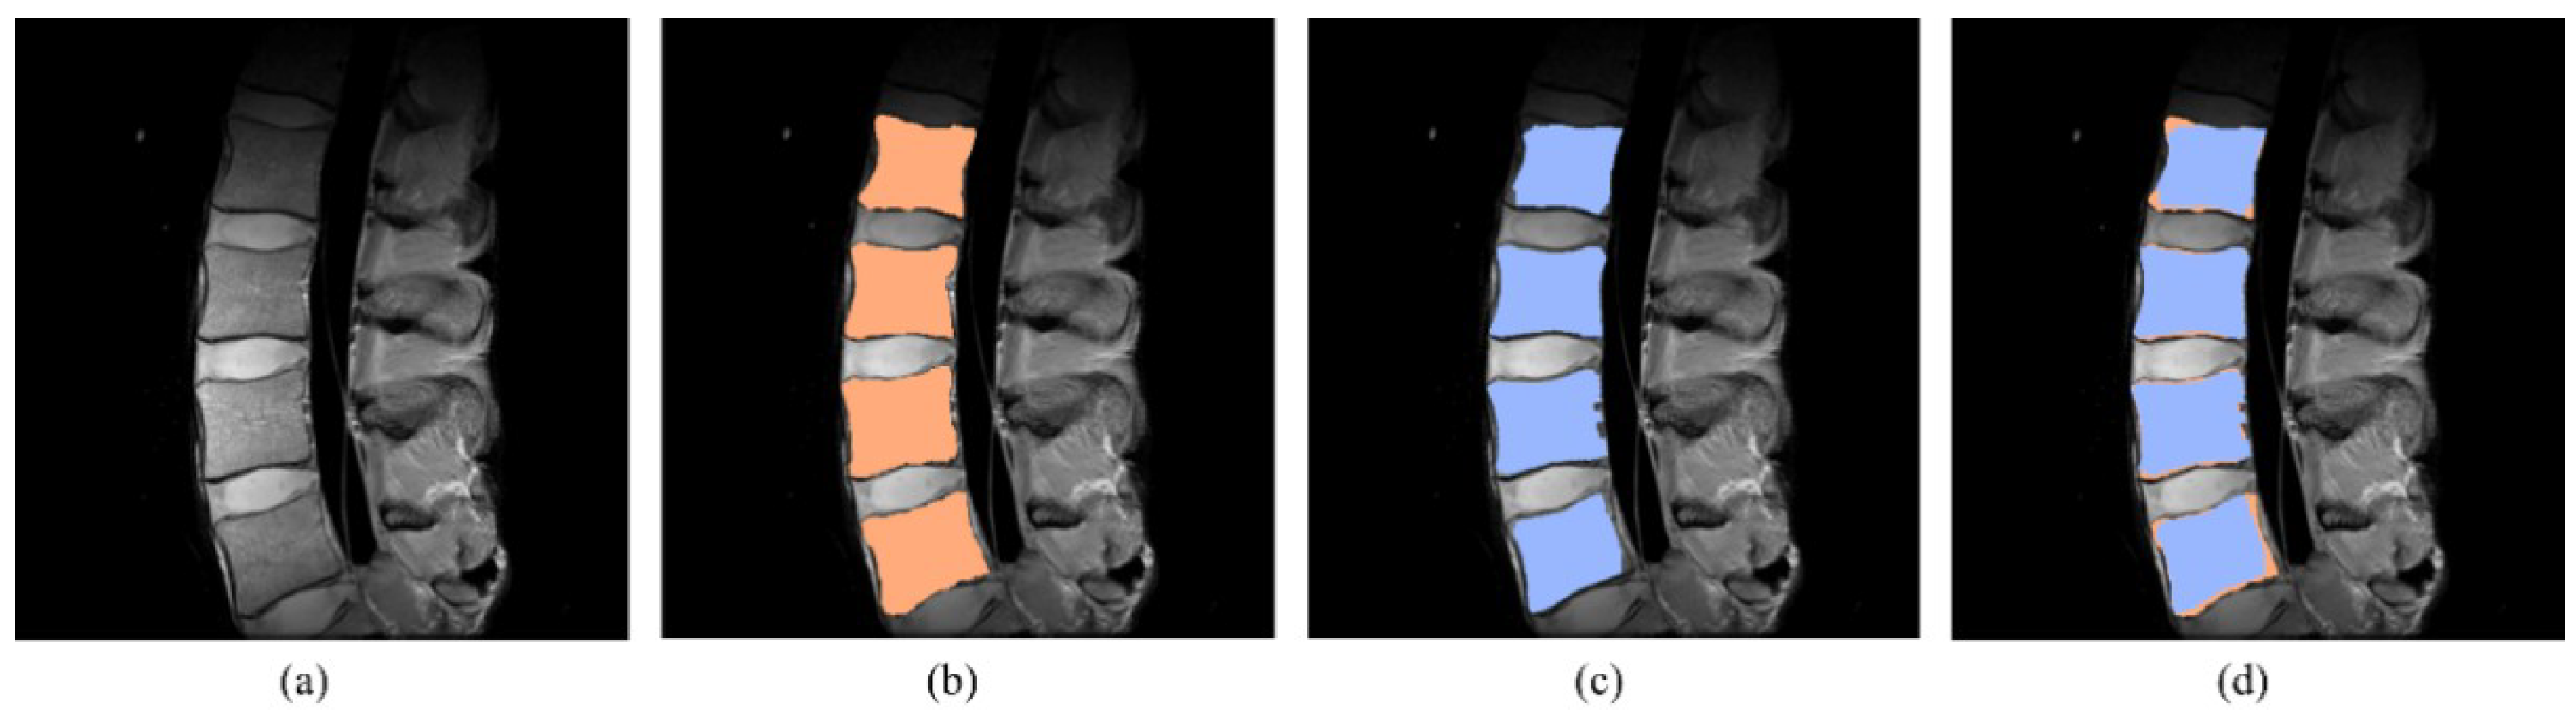

2.4. Segmentation

3. Results and Discussions

3.2. Segmentation Results